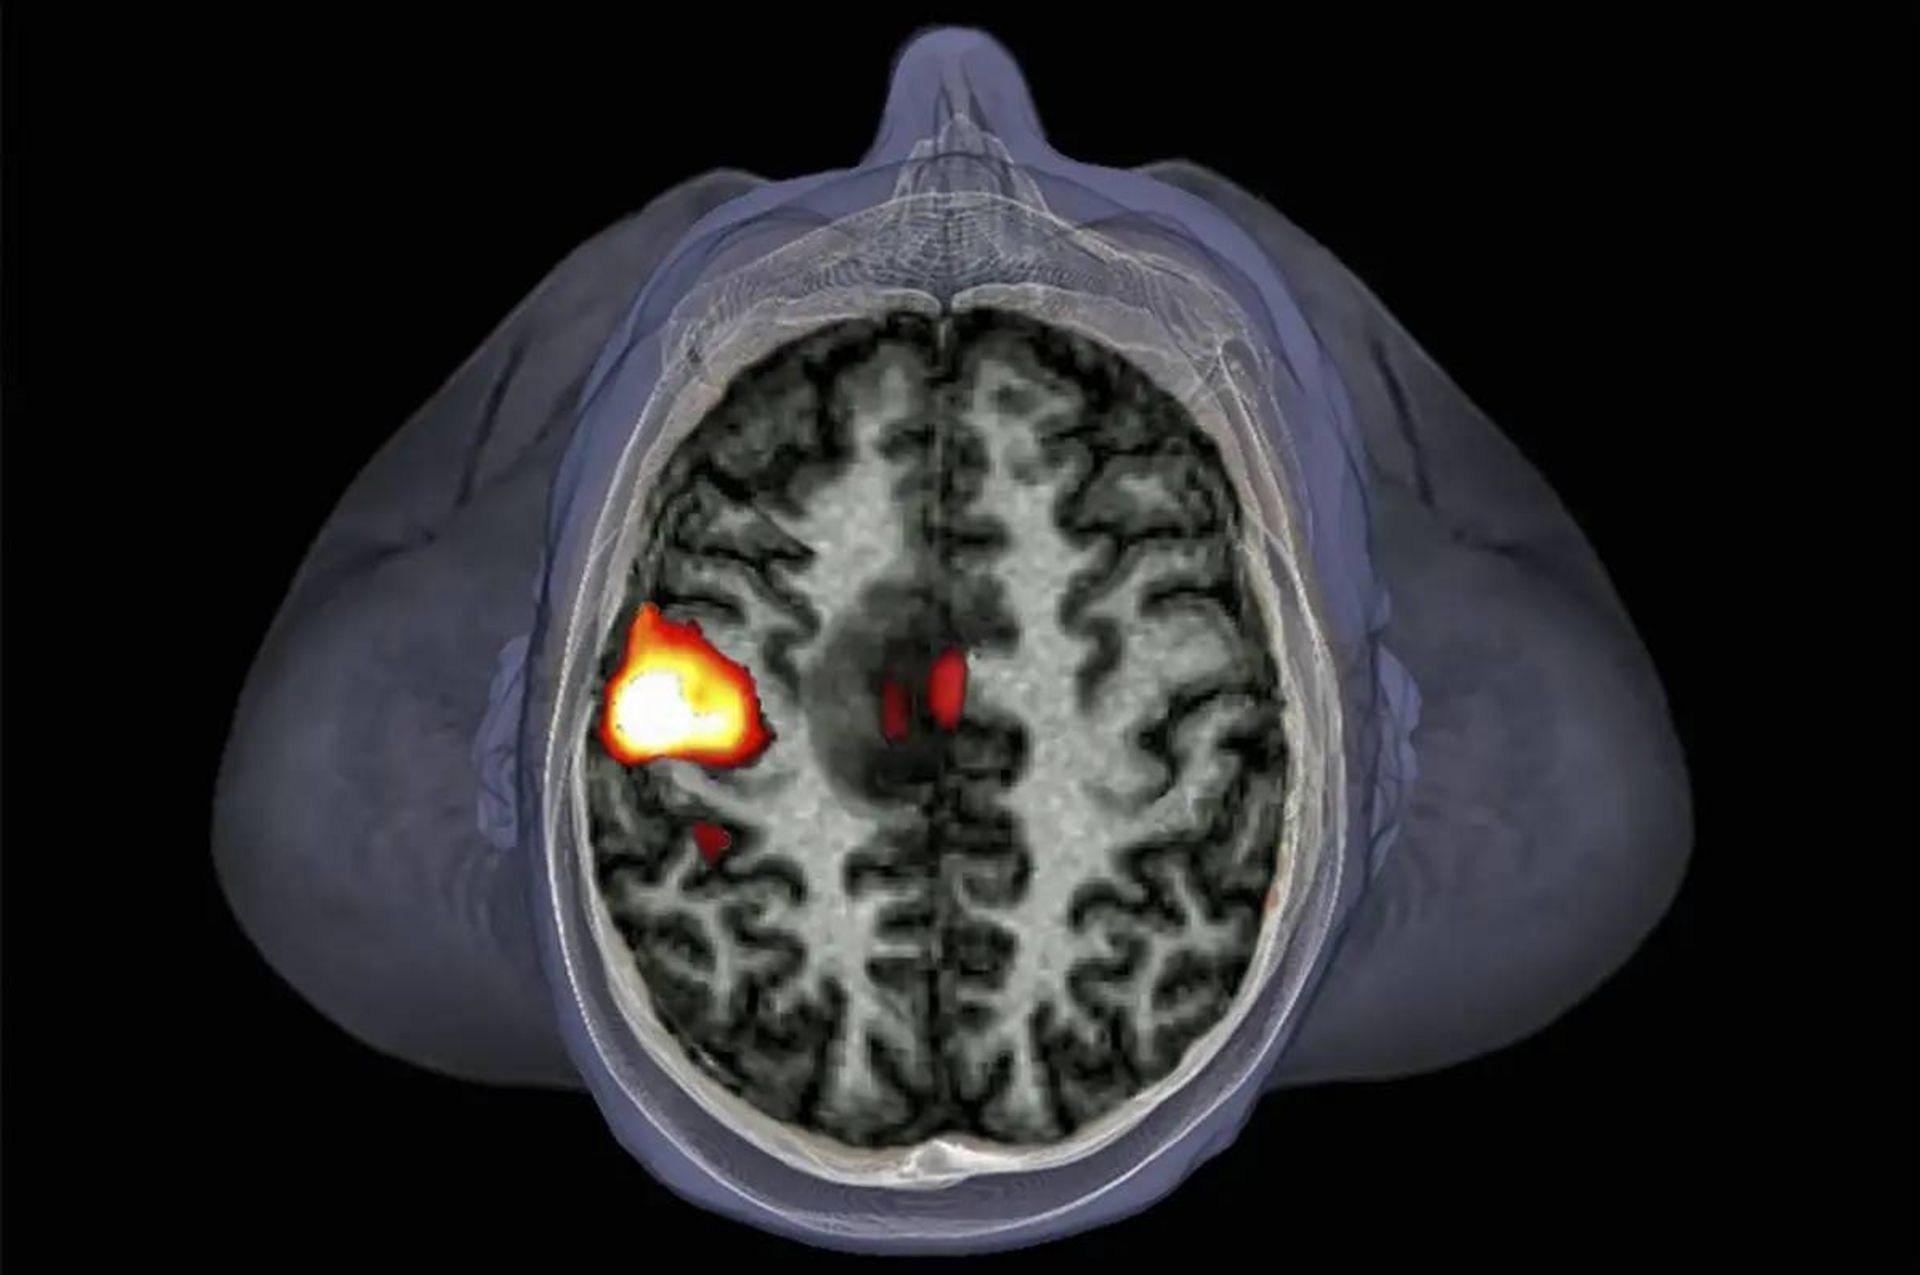

اول از همه باید پرسید ۱۰ درصد از چه چیزی؟ اگر منظور ۱۰ درصد از نواحی مغز باشد، به‌راحتی می‌توان آن را رد کرد. عصب‌شناسان با استفاده از تکنیک تصویرسازی تشدید مغناطیسی کارکردی (fMRI) می‌توانند بررسی کنند که وقتی افراد کار خاصی انجام می‌دهند یا درباره‌ی چیزی فکر می‌کنند، کدام قسمت‌های مغز آن‌ها فعال است.

اسکن مغز

درواقع، درحال‌حاضر fMRI بهترین ابزاری است که برای اندازه‌گیری فعالیت مغز دراختیار داریم. در این روش، فرد در اسکنر لوله‌مانندی دراز می‌کشد و به محرک‌های مختلف پاسخ می‌دهد. اسکنر تغییر جریان خون مغز را اندازه‌گیری می‌کند که نشانگر افزایش مصرف انرژی در مناطق مختلف مغز است. بخش‌هایی از مغز که خون بیشتری دریافت می‌کنند، در حال مصرف انرژی بیشتری هستند؛ بنابراین، ازنظر عملکردی فعال‌تر هستند.

یکی از مسائلی که احتمالاً موجب این تفکر شده، نشانگرهای فعالیت پراکنده‌ی مغز است که در اف‌ام‌آرآی مغز انسان مشاهده می‌شود. فرض کنید درون اسکنر اف‌ام‌آرآی قرار دارید و در حال تماشای فیلم هستید. نواحی خاصی از مغز شما (برای مثال قشر بینایی و قشر شنوایی) بسیار فعال‌تر از نواحی دیگر خواهند بود و این فعالیت در تصاویر fMRI به‌شکل لکه‌های رنگی ظاهر خواهد شد.

لکه‌های رنگی نشانگر فعالیت زیاد معمولاً بخش‌های کوچکی از تصویر مغز و کمتر از ۱۰ درصد آن را دربر می‌گیرند و برای مشاهده‌گر عادی ممکن است این‌طور به‌نظر برسد که بقیه‌ی مغز کاری انجام نمی‌دهد. بااین‌حال، این نوع تصویربرداری تفاوت‌های بزرگ در فعالیت منطقه‌ای مغز را آشکار می‌کند، نه هر کاری که مغز در حال انجام‌دادن آن است.